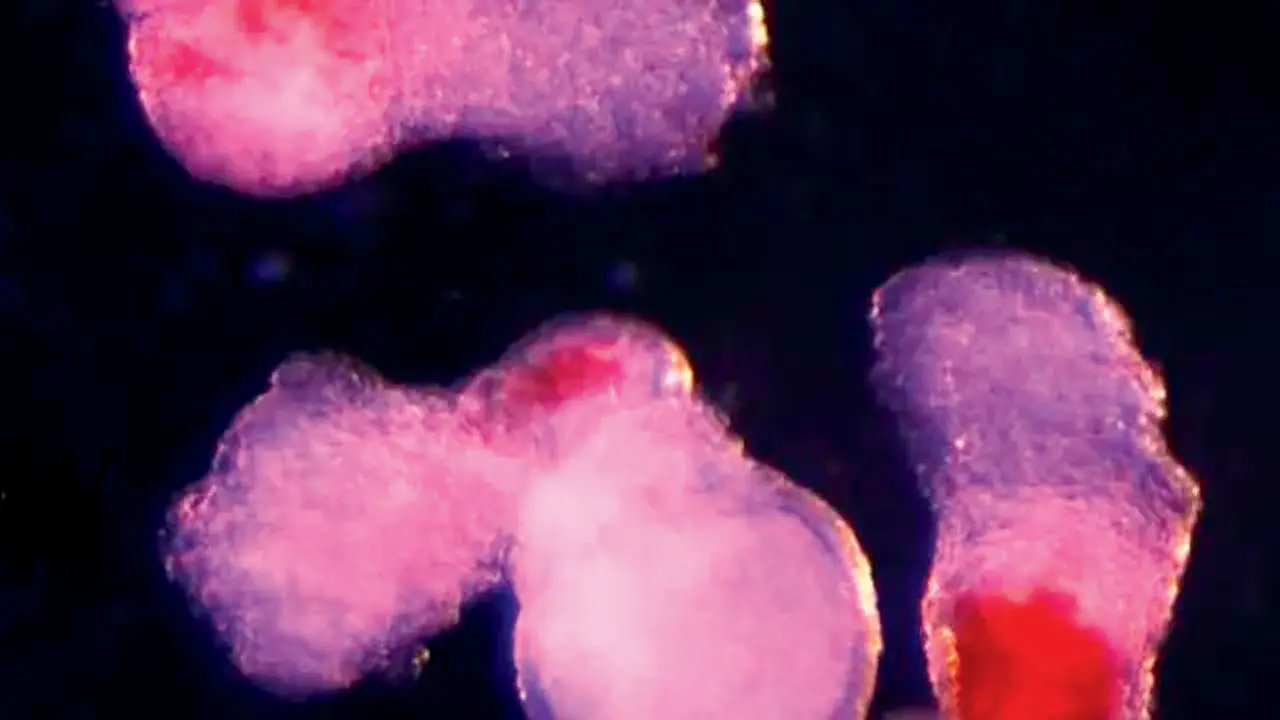

Os cientistas de Cambridge chamam suas estruturas de “hematóides”. Esses aglomerados auto-organizados começam a produzir sangue após cerca de duas semanas no laboratório, imitando o processo observado em embriões humanos. Os hematoides não podem se desenvolver em embriões porque não possuem tecidos como saco vitelino e placenta. Mas as suas capacidades de formação de sangue oferecem uma janela poderosa para o desenvolvimento humano inicial.